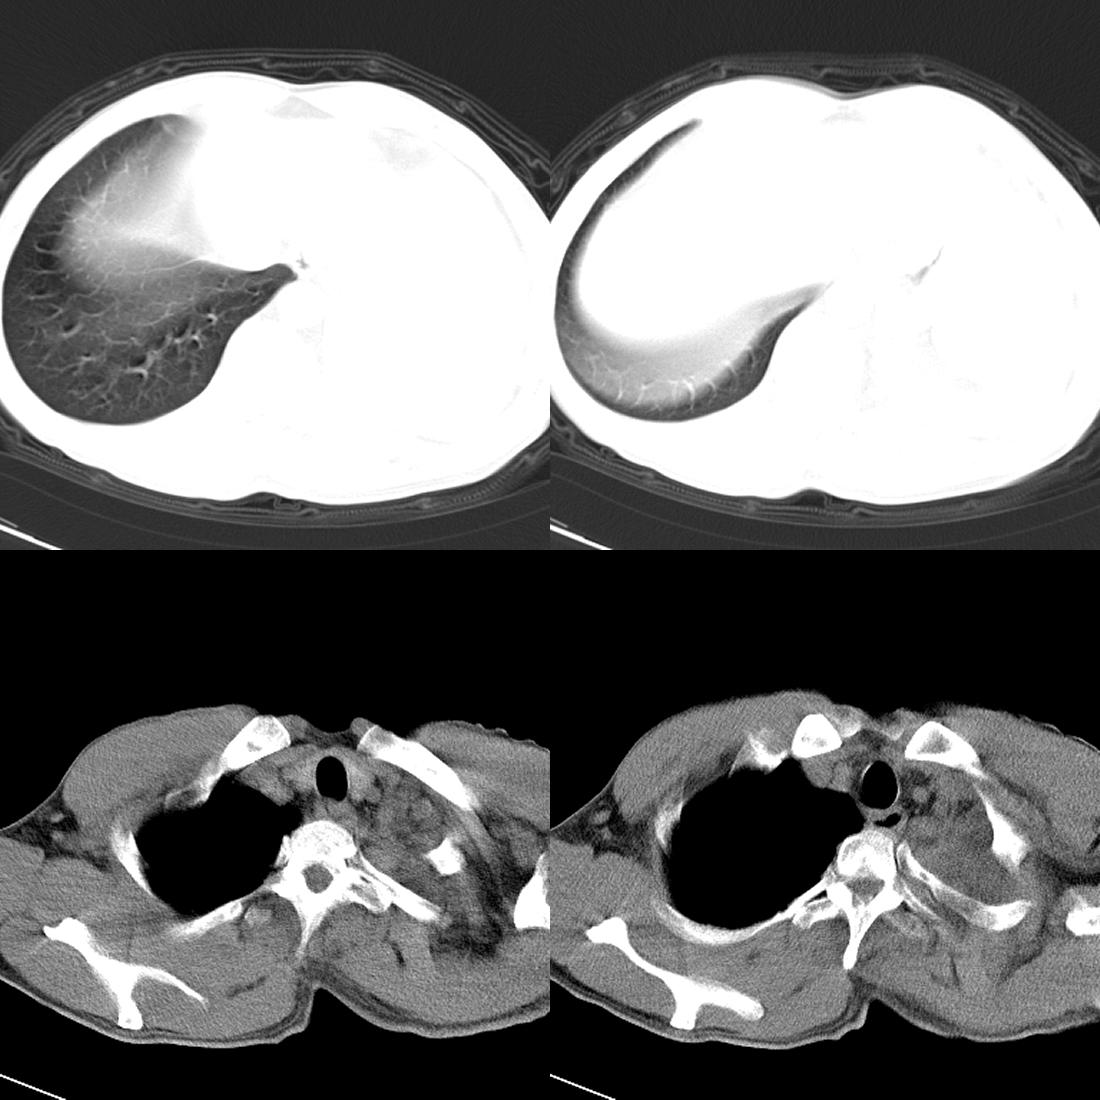

m42y,反复胸背痛数月。无明显的咳嗽、咯痰、咯血症状。

左肺不张 并大量胸腔积液.建议气管镜 除外占位..

左肺上叶周围型肺癌伴肺\\胸膜\\肋骨\\胸椎横突转移,左侧胸腔积液.

左侧椎体、横突、肋骨呈溶骨性破坏,半左侧胸腔中等量积液;左肺尖部可见一肿块影,边界欠清;多考虑恶性骨肿瘤,不除外肺尖部转移性表现可能。

左肺没见明显占位病变,但左肺门增大,不除外肿大淋巴结,左侧肋骨、胸椎融骨性破坏,考虑左侧胸膜恶性病变

左肺上叶周围型肺癌伴双肺\\胸膜\\肋骨\\胸椎横突转移,左侧胸腔积液.